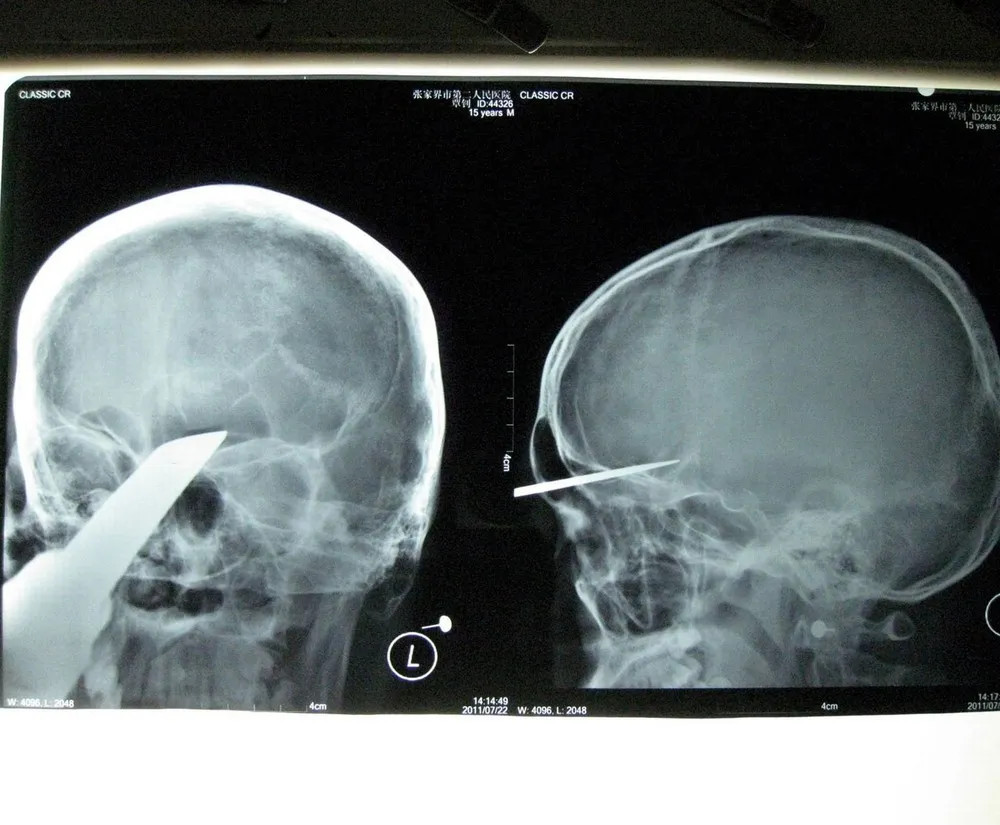

Sword survivor: Obviously you'd take a sword with you when you go round to visit your mate... Zhang Bin, 15, was taken 400km to hospital with 5cm of a 50cm sword embedded in his head. He said later: “Three classmates came to visit me at home and one of them brought a sword. He stood 3-4m away from me. I don't know how the sword could fly to me and stab into my head. I felt sharp pains and a large amount of blood streamed down”. Doctors at his nearest hospital did not feel able to deal with the injury and sent him to another unit four hours away, where the sword was removed in a four hour operation. The chief surgeon commented: “Luckily the knife didn't touch the arteries in the skull and key nerves, otherwise it would have been a different story”. (Photo by Rex Features)